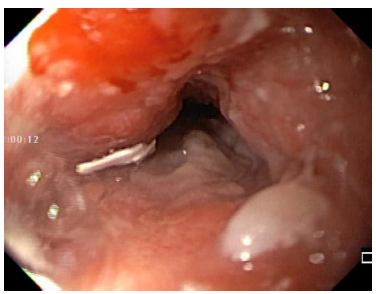

Durante la endoscopia se encuentra lengua de coloración oscura negruzca en su dorso, con aspecto de “pelos”, sin compromiso en los bordes ni en la punta, con zona de despigmentación blanquecina en la zona central posterior (Figuras 1 y 2). En el esófago medio (25 cm), por paredes laterales derecha, izquierda y anterior, hay lesión nodular, infiltrante y friable que produce estenosis franqueable de 12 mm y llega hasta los 30 cm, sin compromiso esofágico distal (Figuras 3 y 4).

Figura 3 Endoscopia. Borde proximal de carcinoma escamocelular de esófago medio que compromete el 80% de la pared y de la luz.

Patología reportó carcinoma de células escamosas grandes, no queratinizante, infiltrante, pobremente diferenciado y ulcerado.